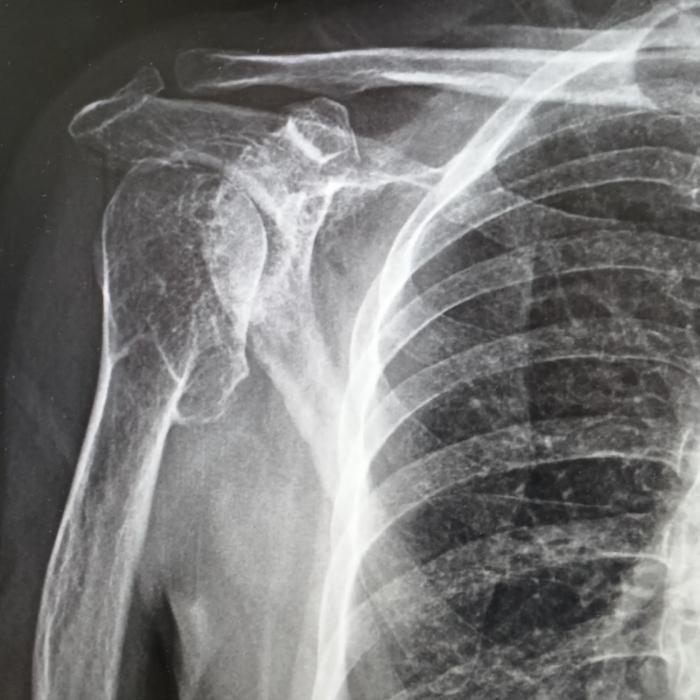

患者右肩疼痛已超過5年,日常梳頭、穿衣均受影響。多次接受針灸、外敷藥等保守治療效果不佳。2025年10月MRI檢查顯示:右肩關(guān)節(jié)嚴(yán)重退行性變,肱骨頭塌陷變形伴多發(fā)骨贅,關(guān)節(jié)腔積液及滑膜炎,同時(shí)存在盂唇損傷與肩袖損傷,岡上肌撕裂伴嚴(yán)重退變。

在成都市第三人民醫(yī)院評(píng)估后明確診斷為右肩關(guān)節(jié)重度骨性關(guān)節(jié)炎伴肩袖損傷。考慮其關(guān)節(jié)結(jié)構(gòu)破壞重、功能需求高,團(tuán)隊(duì)為其制定反式人工肩關(guān)節(jié)置換方案。